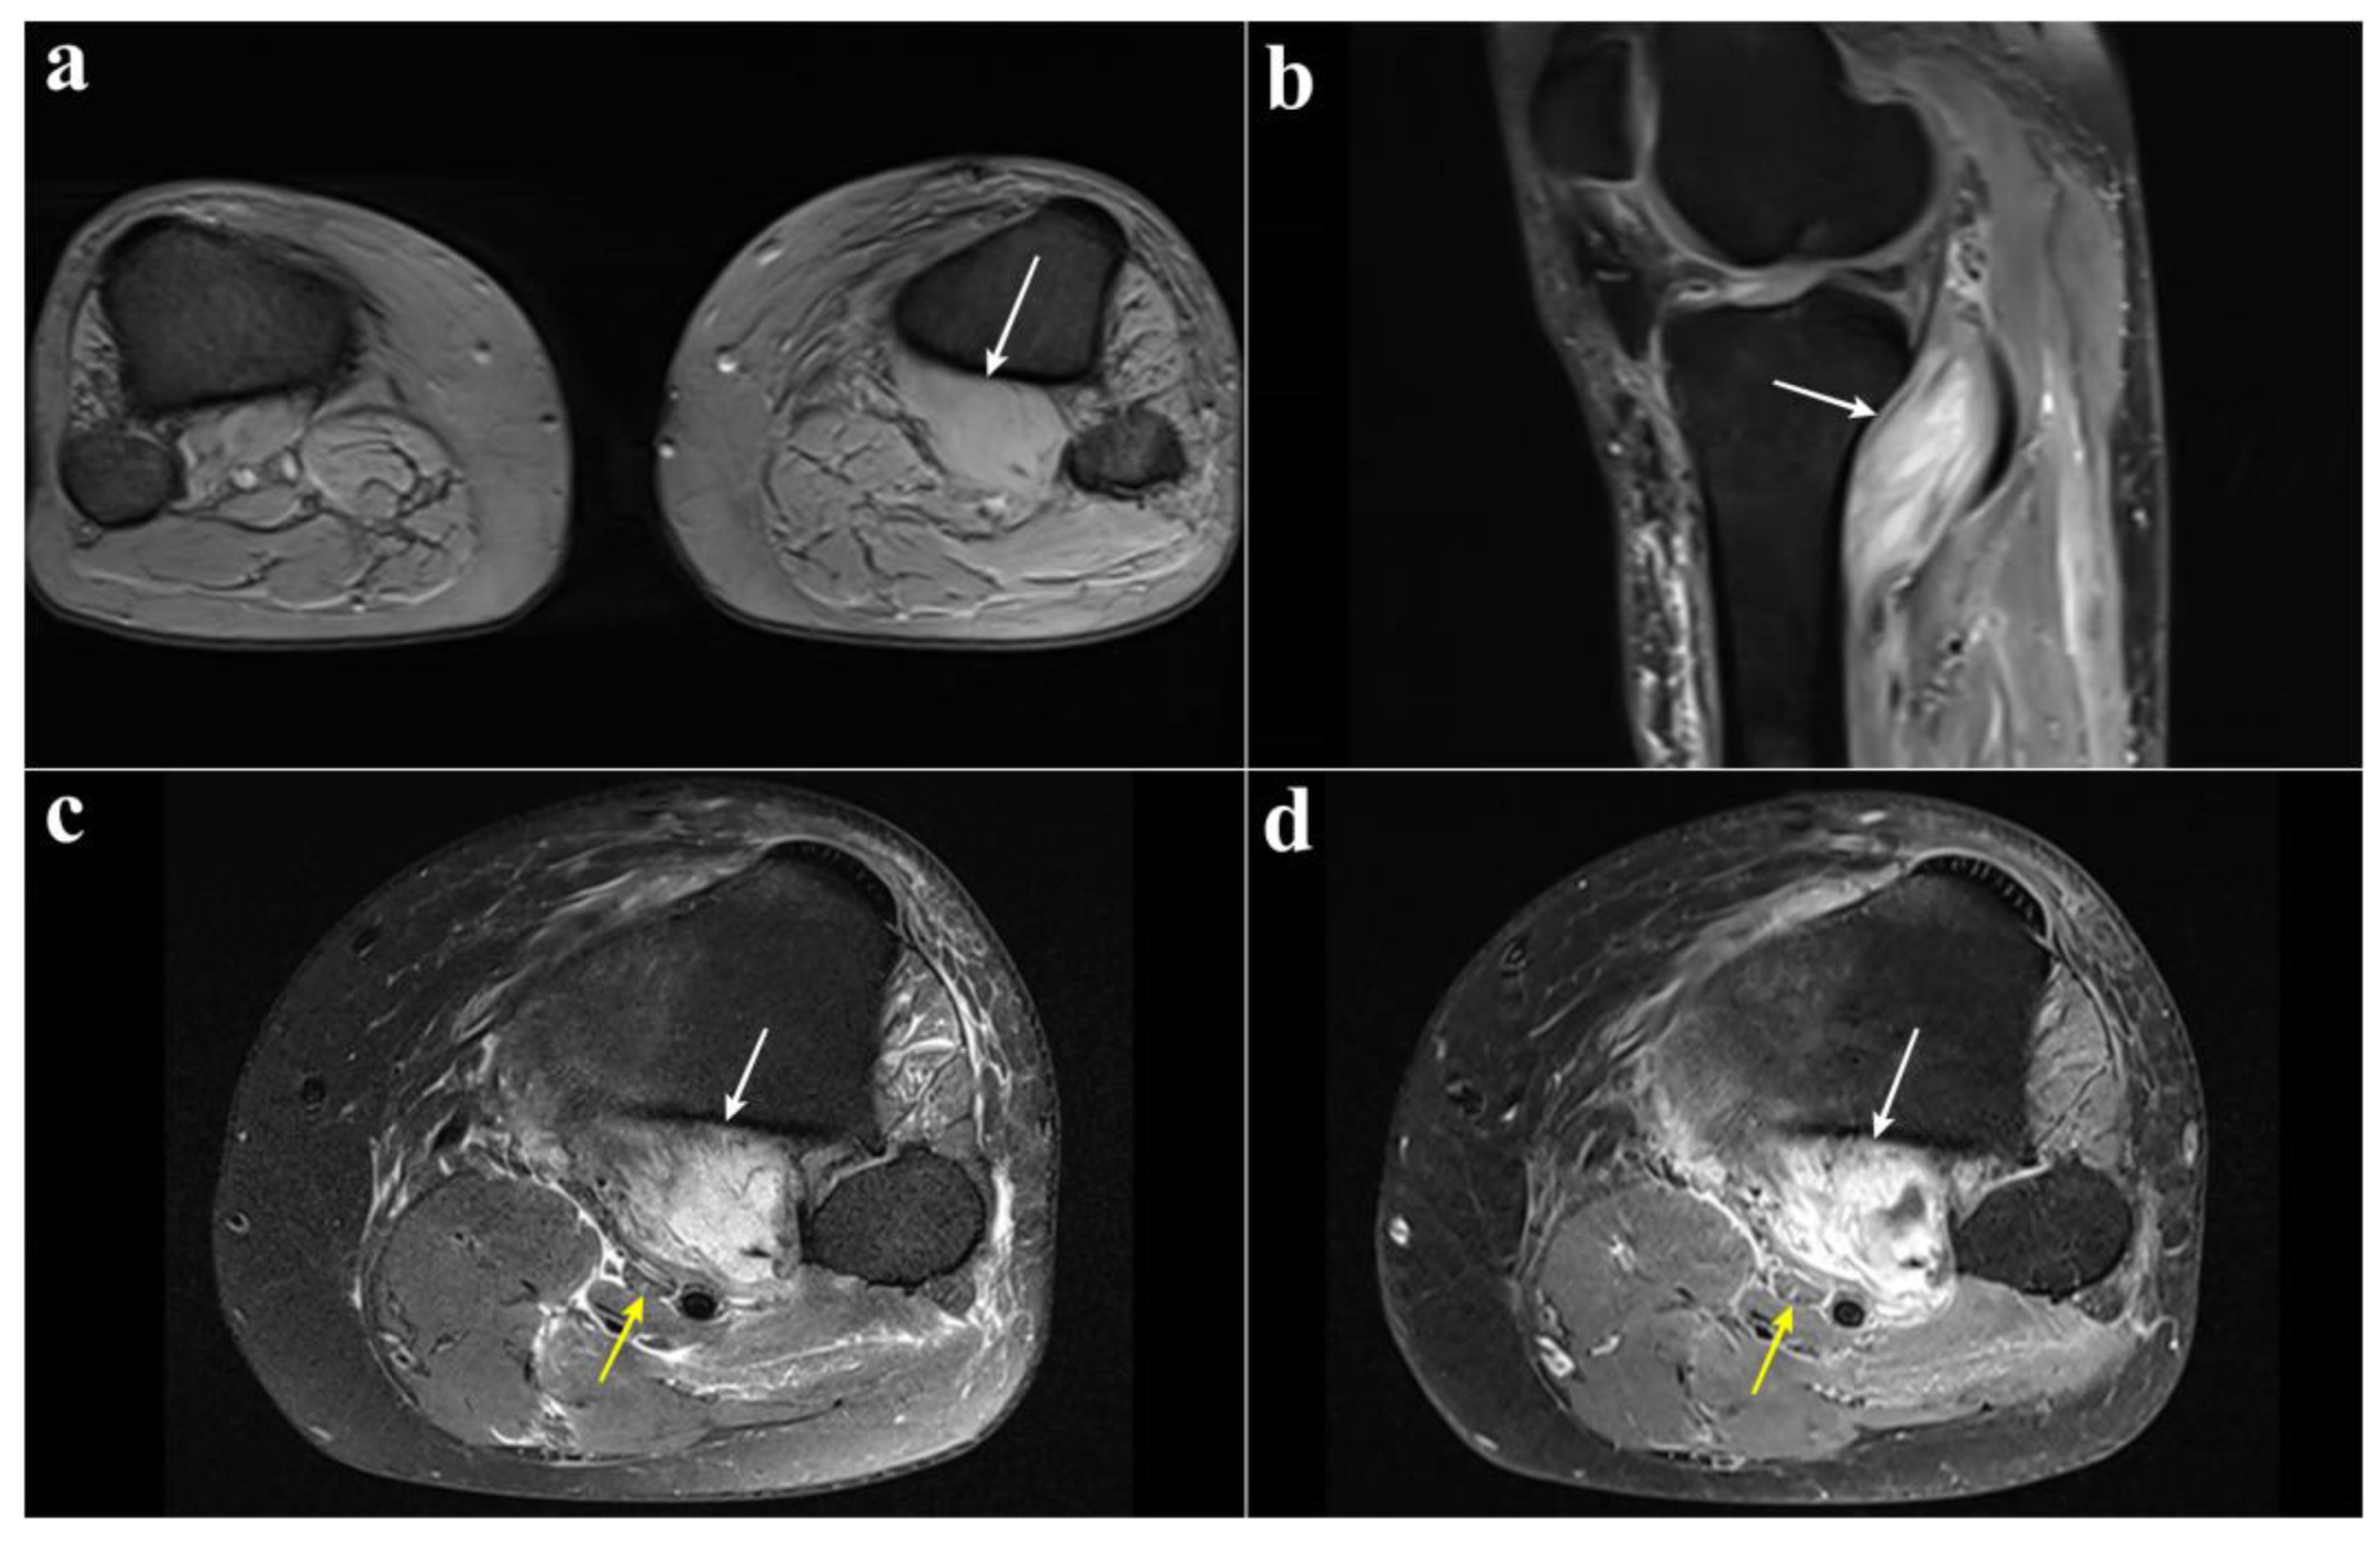

| 59 yo man [2] | Twisting of knee while playing tennis | Pain and swelling right calf; FHL, FDL, and TP: M0; ↓ sensation sole of foot | Venogram: obstruction; X-ray: degenerative changes; MRI: PM rupture and hematoma and TN compression; EMG: TN axonotmesis | Conservative | At 6 months: toe flexion recovered; no further details |

| 59 yo man [14] | Fall from a horse | Biphasic progressive onset; complete TN palsy | X-ray: unremarkable; MRI: PM rupture and hemorrhage and edema and TN Compression | Conservative | At 24 months: toe flexion deficit; intrinsic palsy; protective sensation sole of the foot |

| 34 yo man [11] | Twisting injury | Biphasic progressive onset; immediate posterior knee pain; altered sensation sole of foot; toes flexion: M0 | X-ray: unremarkable; MRI: PM rupture and necrosis and compression popliteal vein and TN | Neurolysis posterior approach | At 9 months: medial sensation recovered; FHL: M1; plantar flexion: M5 |

| 54 yo man [15] | Jump with knee hyperextension | Biphasic progressive onset; posterior knee pain; toe flexion weakness; loss sensation sole of foot; absent Achilles reflex | MRI: PM thickness, edema, and hemorrhage; EMG: TN palsy | Conservative | At 15 months: moderate improvement toe flexion, persistent pain, and sensory loss |

| 57 yo man [13] | No trauma | Pain left calf; numbness sole of foot; FHL: M1; progressive worsening of symptoms | AngioCT: popliteal artery stenosis; MRI: PM edema and enlargement; EMG: TN palsy | Neurolysis posterior approach | Immediate pain relief after surgery. At 2 months: partial deficit; FHL still impaired |